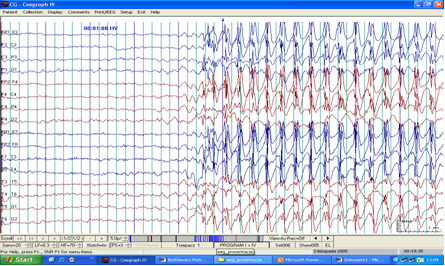

Poniższy zapis czynności bioelektrycznej mózgu został wykonany u 8-letniego dziecka w czuwaniu. W czasie hiperwentylacji (HV) zauważono kilkusekundowe znieruchomienie dziecka i zarejestrowano wyładowania uogólnione zespołów iglicy z falą wolną o częstotliwości 3 Hz. Całość obrazu może odpowiadać: